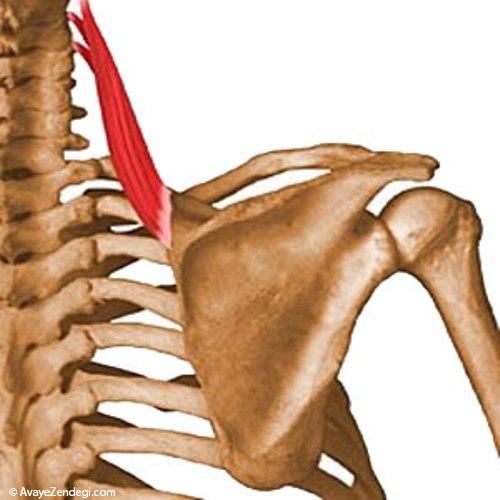

عضله گوشه ای

تارهای این عضله از روی زوائد عرضی چهار مهره اول گرد به پایین و خارج کشیده شده و به قسمت فوقانی لبه داخلی استخوان کتف بین زوایه فوقانی و ریشه خار کتف چسبندگی پیدا می کنند.